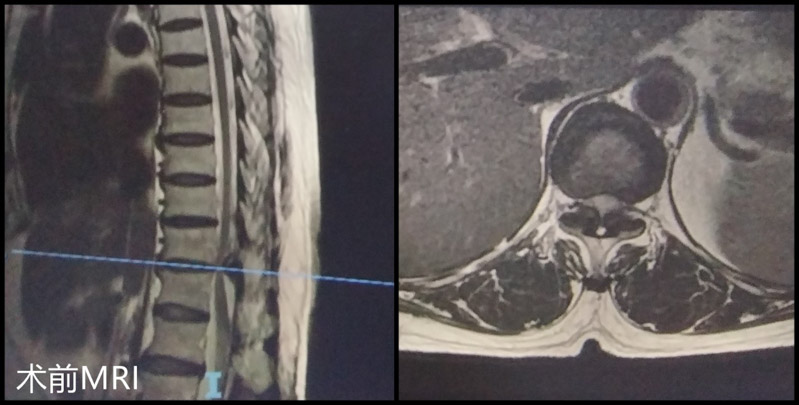

▲根據胸腰椎磁共振顯見T11/12黃韌帶骨化、T11/12脊髓變性、T11/12椎管狹窄嚴重

完善相關檢查后,柳州市人民醫院脊柱外科團隊就患者的病情進行了科內討論,一致認為患者已經做過腰椎開放減壓融合內固定手術,但術后癥狀未緩解,考慮其目前癥狀為脊髓變性引起的黃韌帶骨化繼發胸椎管狹窄,需盡早手術解除脊髓壓迫。